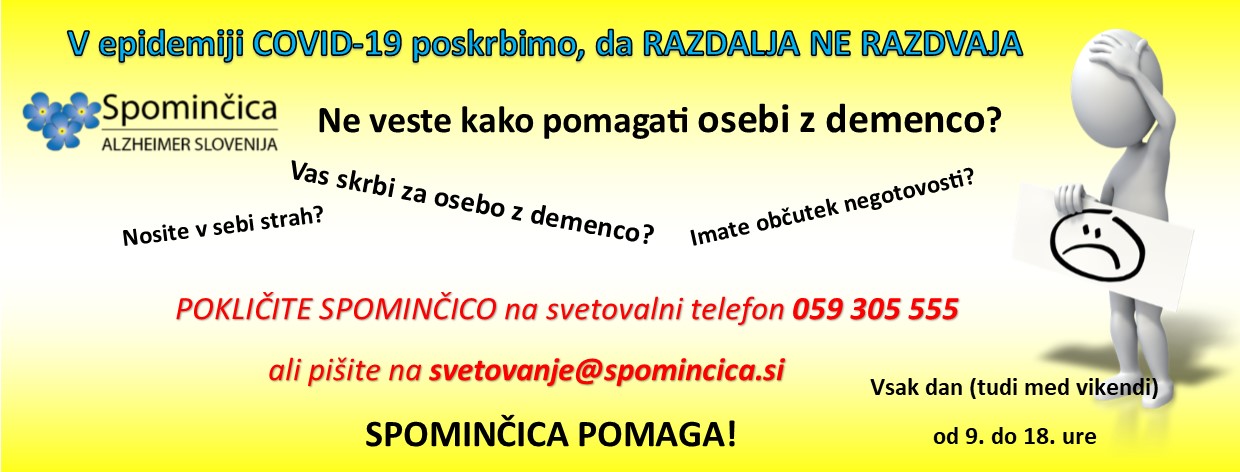

Sociala

Zdravje